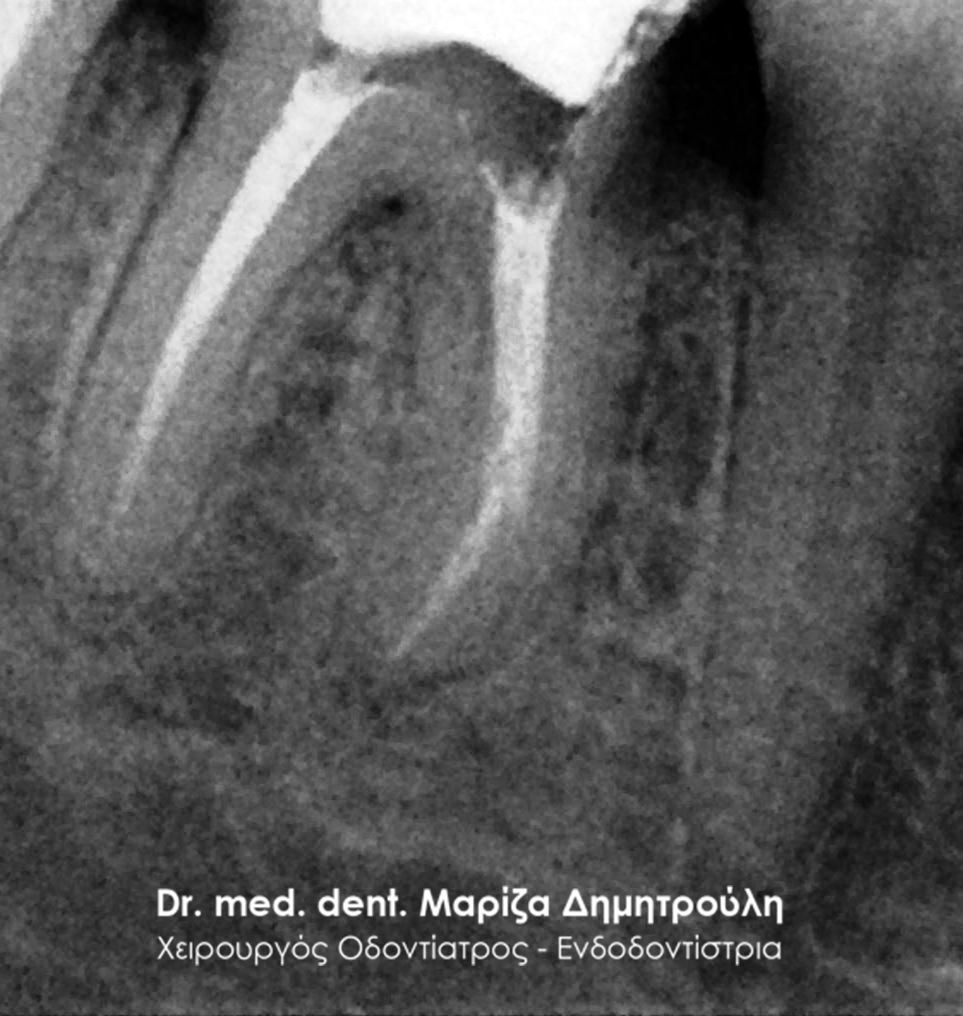

Η ασθενής προσήλθε με έντονο πόνο στο ιατρείο και είχε λάβει τις προηγούμενες μέρες αντιβίωση, εφόσον στην άνω αριστερή πλευρά της είχε οίδημα. Μετά την κλινική εξέταση διαπιστώθηκε η ύπαρξη ενός συριγγίου υπερώια μεταξύ των δύο άνω αριστερών γομφίων. Πραγματοποιήθηκε ακτινογραφία με την τοποθέτηση ενός κώνου γουταπέρκας για τη διάγνωση του υπαίτιου δοντιού, που είχε προκαλέσει την εμφάνιση του συριγγίου. Σύμφωνα με όσα αποκάλυψαν η κλινική και ακτινογραφική εξέταση ακολούθησε η έναρξη απονεύρωσης στο δεύτερο άνω αριστερό γομφίο, δεδομένου οτι είχε ένα βαθύ λευκό σφράγισμα ρητίνης που εκτεινόταν στο ύψος του νεύρου του δοντιού. Το δόντι είχε έντονα συμπτώματα πόνου κατά την επίκρουσή του.

Μετά την ολοκλήρωση της απονεύρωσης στο δεύτερο άνω αριστερό γομφίο το δόντι είναι ασυμπτωματικό. Η αποκατάσταση του δοντιού πραγματοποιήθηκε με λευκό σφράγισμα ρητίνης, εφόσον το έλλειμμα των οδοντικών ιστών ήταν μικρό και δε χρειαζόταν η προστασία του δοντιού με θήκη / στεφάνη δοντιού.

Σε δεύτερη φάση θα ακολουθήσει η επανάληψη απονεύρωσης στον πρώτο άνω αριστερό γομφίο, καθώς η απονεύρωση του δεν καλύπτει όλο το μήκος των ριζών του δοντιού και το δόντι μετά το πέρας της ενδοδοντικής θεραπείας συνεχίζει να πονά.

ΜΕΤΑ